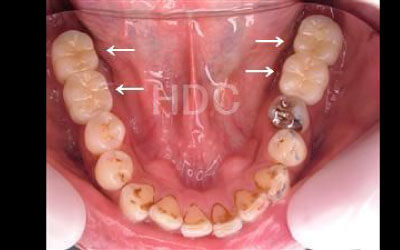

2 歯が傾いてくる、落ちてくる

歯は互いに支え合い、バランスを保っています。そのため、歯が抜けると支えがなくなり、抜けた部分の両隣の歯が傾いたり、上の歯が下に移動してきたりすることがあります。